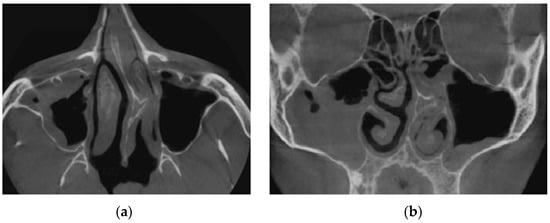

Figure 16 demonstrates the state of the nasal cavity with adenoid vegetations, which can be seen in the images of characteristic sections in axial (Figure 16a) and sagittal (Figure 16b) projections.

Figure 17 represents tomographic data of a patient with empty nose syndrome after bilateral conchotomy. The removal of the lower shells and enlarged air space in the nasal cavity are clearly visualized in the axial (Figure 17a) and frontal (Figure 17b) projections.